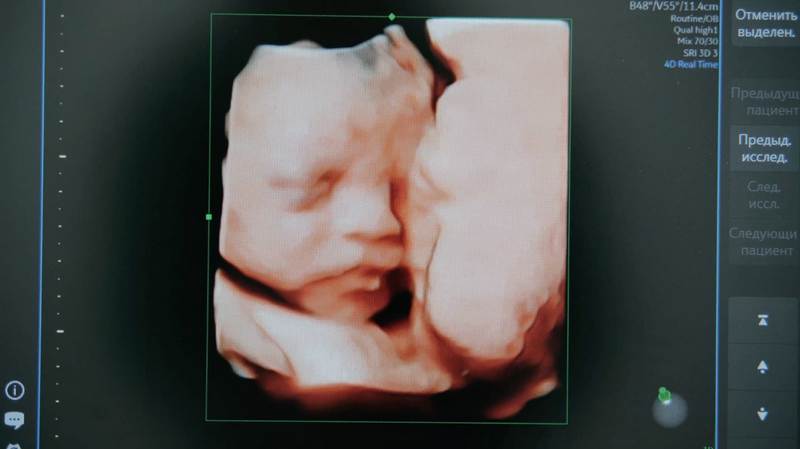

В основе разработки — система искусственного интеллекта для анализа снимков УЗИ, созданная на базе облачной платформы Yandex Cloud и экспертизы Центра технологий для общества. Технология предназначена для работы со снимками первого скрининга, проводимого на 11—14 неделе беременности.

Дополнительное оборудование не потребуется: установят только программное обеспечение. Система будет применяться при первом скрининге и анализировать результаты УЗИ беременных с использованием искусственного интеллекта. Обрабатываться будут исключительно изображения без использования персональных данных пациентов. Для хранения, обработки данных и обучения нейросетей станут применять облачные технологии Yandex Cloud.

— Технологии Yandex Cloud применяются во многих социально значимых проектах, и раннее обнаружение признаков spina bifida — это ещё одна важная задача, с которой мы можем помочь. Нейросеть станет ассистентом врача, обеспечивая поддержку принятия решений. Компетенции врача необходимы для финальной оценки и принятия дальнейших решений, а облачные и ИИ-технологии позволяют распознавать на снимках мельчайшие детали, которые может пропустить человеческий глаз, — отметила руководитель Центра технологий для общества при Yandex Qazaqstan Анна Лемякина.

Spina bifida — врождённое заболевание, при котором у плода неправильно формируется позвоночник и спинной мозг. Встречается примерно у одного из тысячи новорождённых. В тяжёлых формах заболевание приводит к параличу и нарушениям работы внутренних органов. Ранняя диагностика повышает шансы на своевременное лечение, включая возможность внутриутробной операции до 26-й недели беременности.